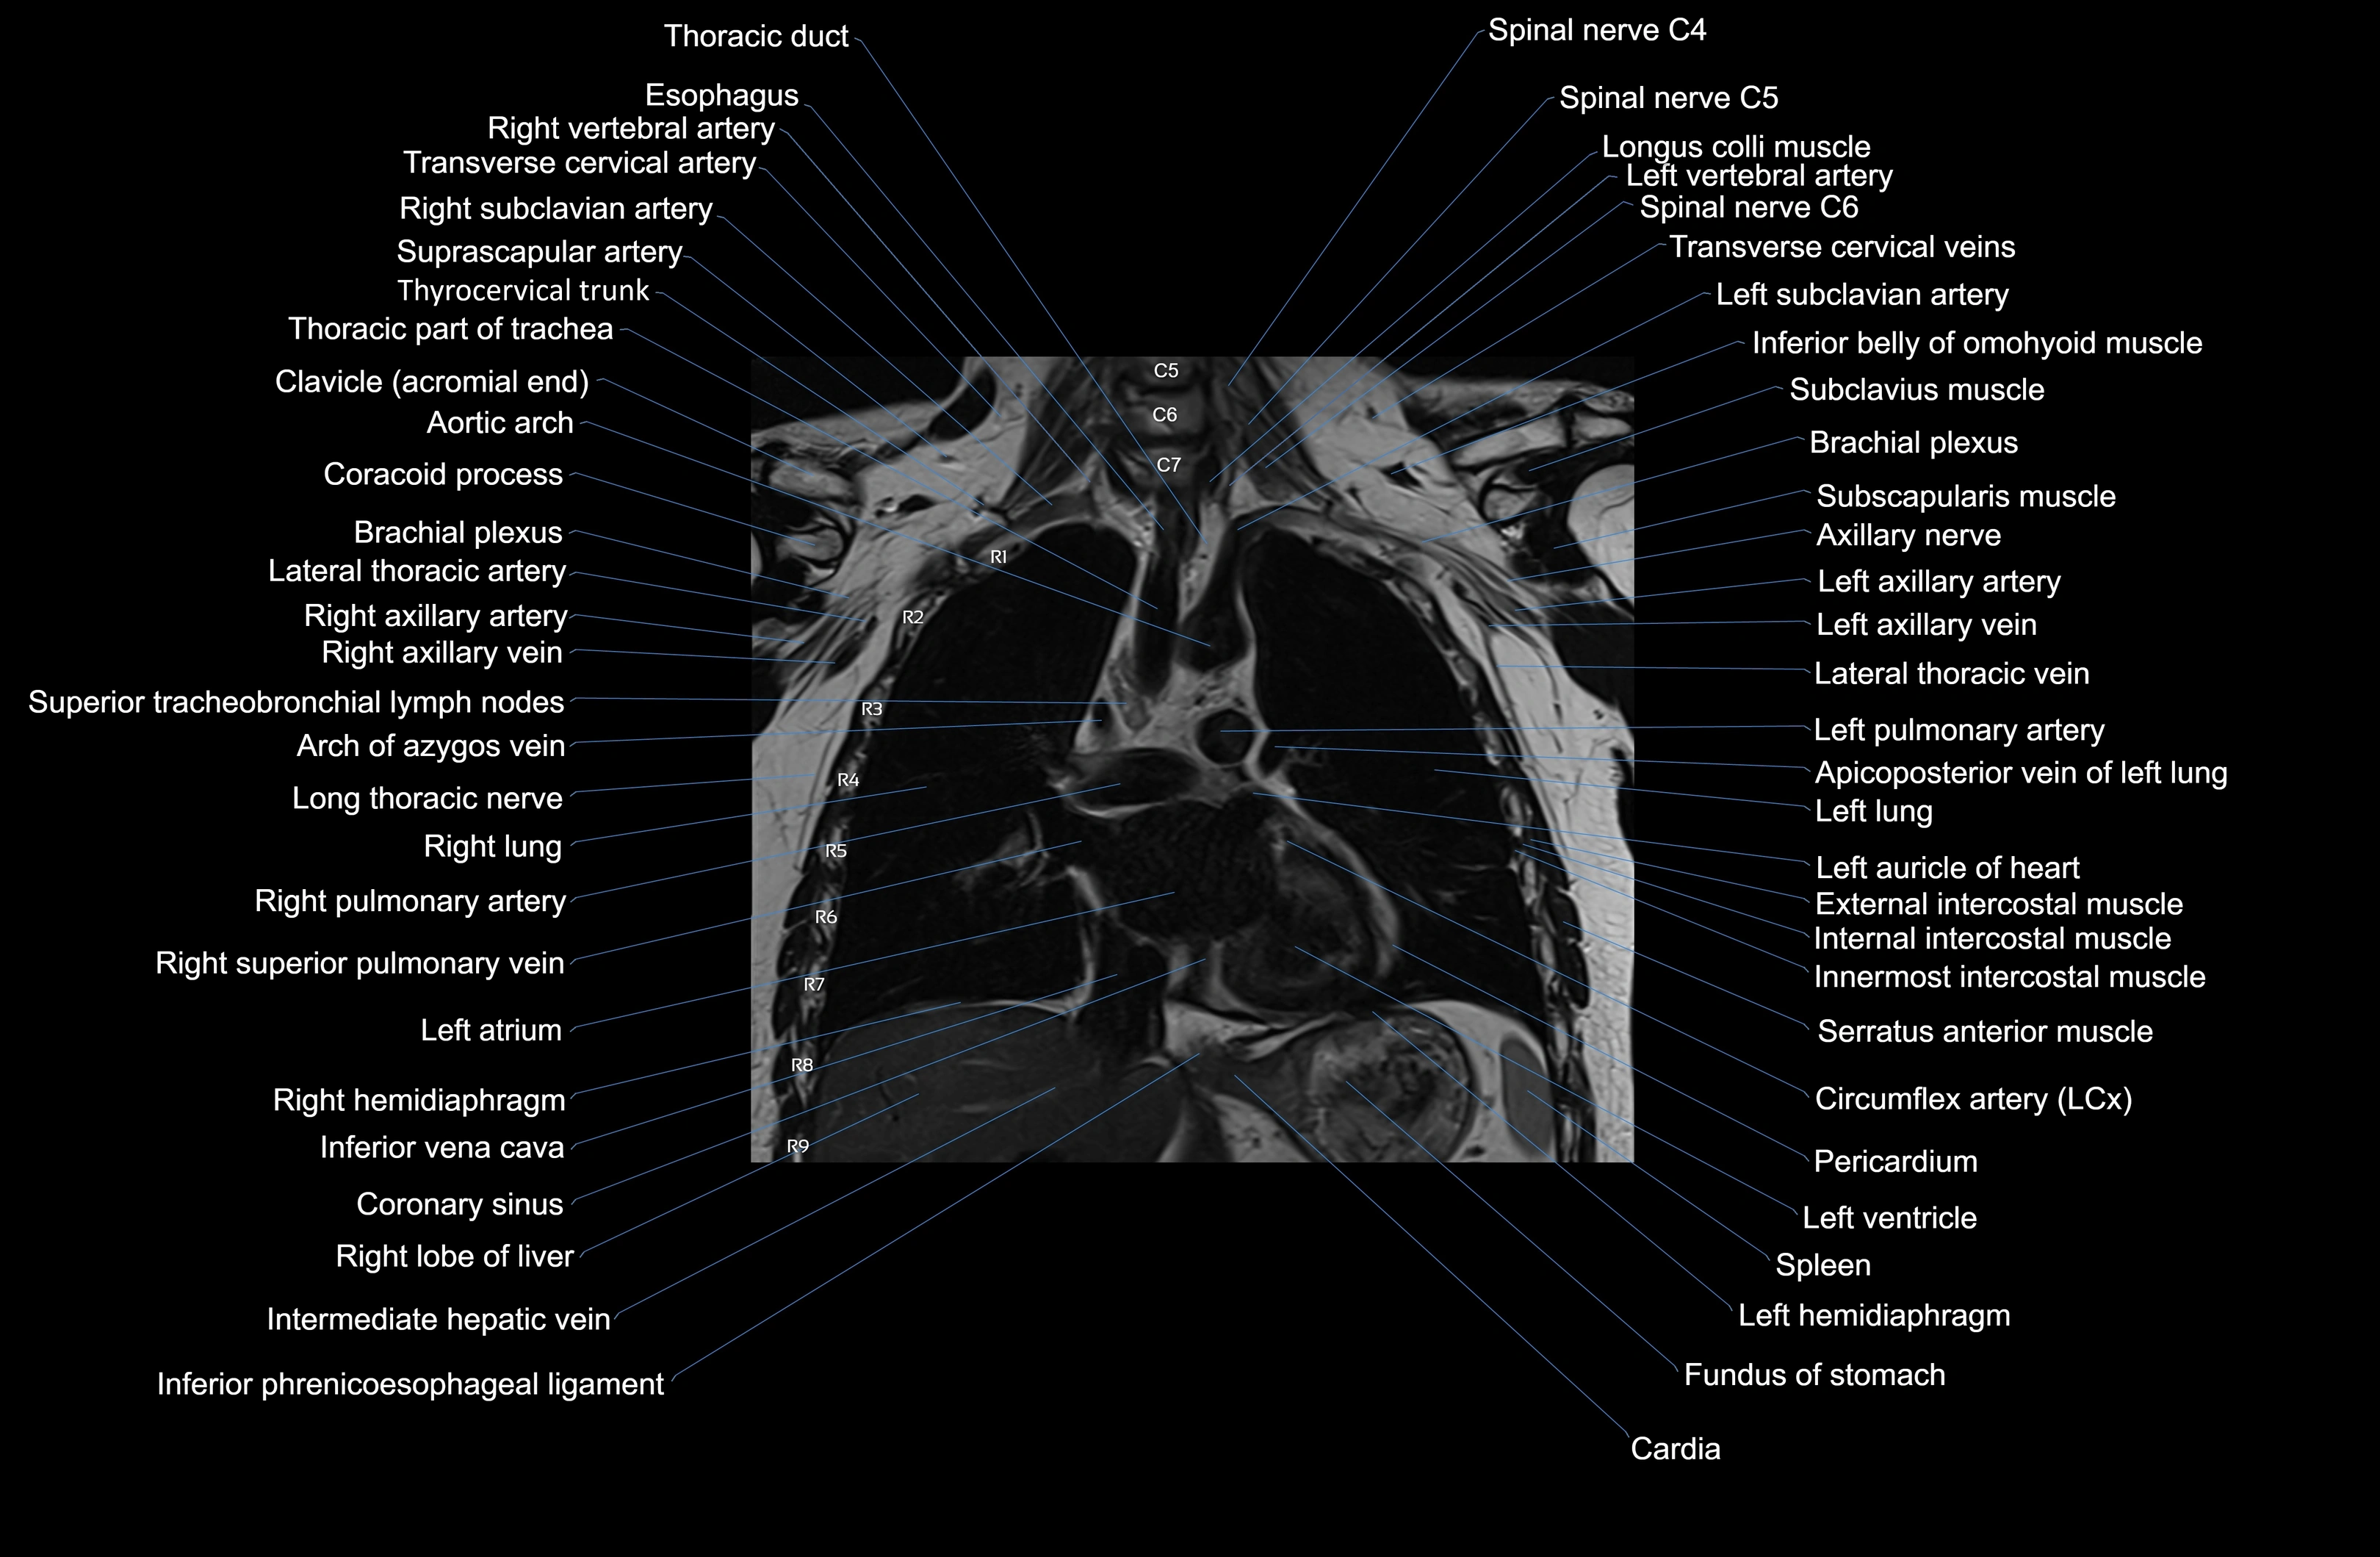

MRI images